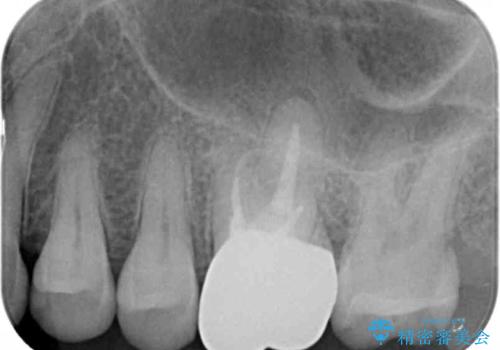

- 銀歯が取れたのち放置してしまいセラミック治療を希望され来院されました。

虫歯の再発も見られたので、丁寧に虫歯を取り除いたのち根管治療を行いジルコニアクラウン・セラミックインレーにより修復処置を行いました。